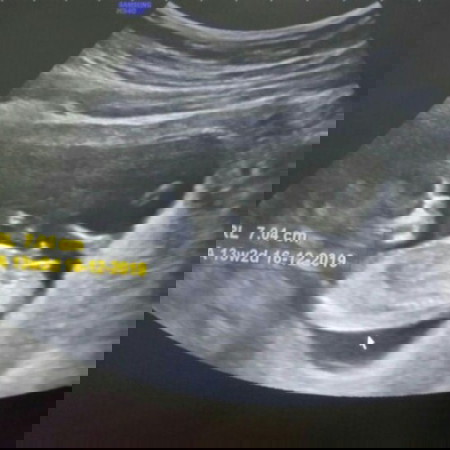

13w 2d สามารถดูเพศได้รึยังคะ หมอไม่ยอมบอกเพศลูก

หรือยังไม่ชัดเจน